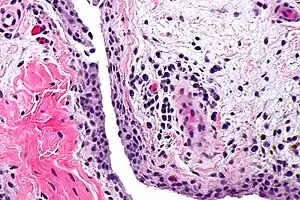

| Chronic synovitis | |

Synovitis is the medical term for inflammation of the synovial membrane. This membrane lines joints that possess cavities, known as synovial joints. The condition is usually painful, particularly when the joint is moved. The joint usually swells due to synovial fluid collection. Synovitis may occur in association with arthritis as well as lupus, gout, and other conditions. Synovitis is more commonly found in rheumatoid arthritis than in other forms of arthritis, and can thus serve as a distinguishing factor, although it is also present in many joints affected with osteoarthritis.[1][2] In rheumatoid arthritis, the fibroblast-like synoviocytes, highly specialized mesenchymal cells found in the synovial membrane, play an active and prominent role in the synovitis.[3] Long term occurrence of synovitis can result in degeneration of the joint.